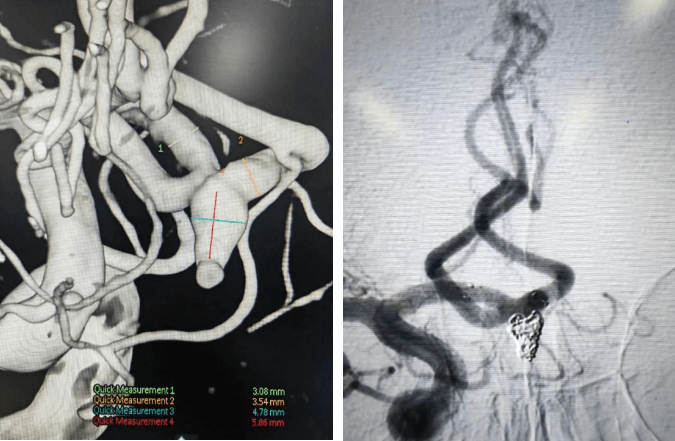

支架辅助动脉瘤栓塞术前、术后对比